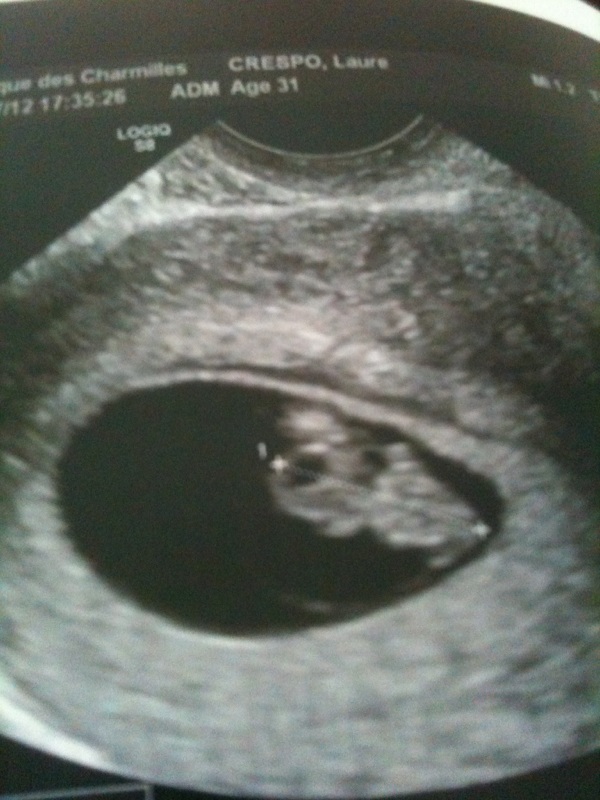

bon alors moi j'ai vu ma crevetteil mesure 15mm mon bébé et son petit coeur bat très vite 162pul voilas je suis rassuré contente et impatiente de le revoir ca va aller vite après les vacances prochaine écho.

je suis de 7semaines am et 7 jours!